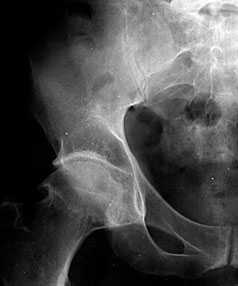

Рис. 1. Обзорная Rо-графия тазобедренного сустава в прямой проекции.

Деформирующий остеоартроз II ст. по Kollgren. Крупные остеофиты на краях суставных поверхностей. Грибовидная деформация бедренной головки

В начальных стадиях (1-2 стадии по Kellgren) ОА тазобедренных суставов при рентгенологическом исследовании определяются: незначительное сужение суставной щели, слабовыраженный субхондральный остеосклероз, точечные кальцификаты в области наружного края крыши вертлужной впадины (зачаток остеофитов), заострение краев ямки бедренной головки в области прикрепления круглой связки бедренной головки (рис. 1).

В поздних стадиях заболевания (соответствует 3-4 стадии ОА по Kellgren) отмечаются:

• прогрессирующее сужение суставной щели

• формирование различной формы и размеров остеофитов на краях суставных поверхностей вертлужной впадины, бедренной головки, отчего она со временем приобретает грибовидную форму. В средней части вертлужной впадины возможно формирование клиновидного остеофита, который может обусловить латеральное смещение бедренной головки

• углубление вертлужной впадины может быть связано с развитием остеофитов; протрузия ее возможна на фоне остеопороза или истончения костей, составляющих дно вертлужной впадины

• выраженный субхондральный остеосклероз. Проявляется в первую очередь в области крыши вертлужной впадины, затем в верхнем отделе бедренной головки

• в далеко зашедших случаях - уменьшение в объеме и уплощение суставной поверхности бедренной головки на фоне выраженной кистовидной перестройки костной ткани, чередующейся с участками субхондрального остеосклероза. Костные кисты могут быть единичными или множественными. Возникают они в верхней части вертлужной впадины или в зоне наибольшей нагрузки на суставную поверхность бедренной головки

• асептический некроз бедренной головки

• подвывихи бедренной кости чаще вверх и латерально, реже вверх и медиально

• уплотнение костной ткани и укорочение шейки бедренной кости.